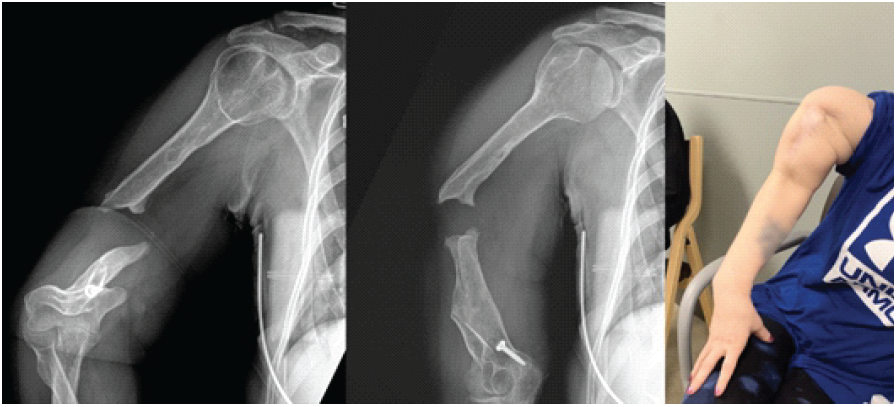

A 41-year-old female presented to the orthopedic clinic with complaints of chronic right arm pain and disability. The patient had a history of previous right humeral shaft fracture treated with an intramedullary nail 5 years prior. This was then complicated by infection. The nail was explanted, the wound irrigated, and the patient was put on IV antibiotics. After nail explanation, the patient did not receive any further orthopedic surgical intervention. Of note, the patient had a medical history significant for bulimia and alcoholism at the time of her initial treatment. On examination, the patient was neurovascularly intact with a well healed surgical incision. The patient had gross motion about her previous fracture site and was unable to extend her arm as a singular unit. Radiographs demonstrated an atrophic non-union about the humeral shaft (Fig. 1).

Figure 1: Pre-operative radiographs and clinical photo; pre-operative anteroposterior and attempted lateral radiographs of the right humerus illustrating a humeral shaft non-union. Pre-operative clinical photo demonstrating the instability of the humeral non-union.